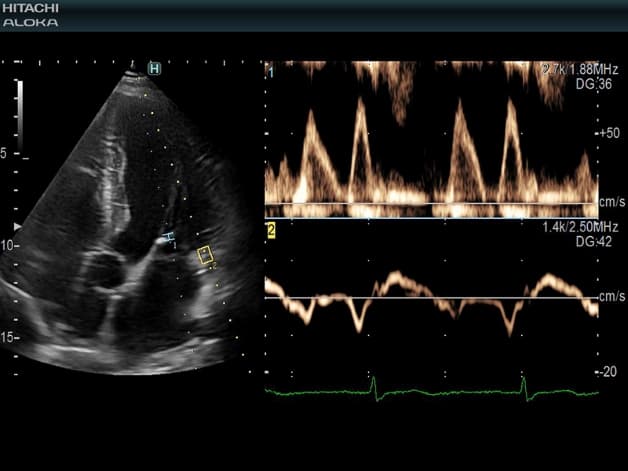

Đây là một chẩn đoán hình ảnh sử dụng sóng siêu âm tần số cao để thu được những hình ảnh động về tim và những cấu trúc liên quan đến tim.

Siêu âm về tim sử dụng sóng siêu âm tần số cao để thu được những hình ảnh động của tim và những cấu trúc liên quan đến tim.

Phương pháp này được chỉ định để đo vận tốc dòng máu ở các vị trí khác nhau trong buồng tim.